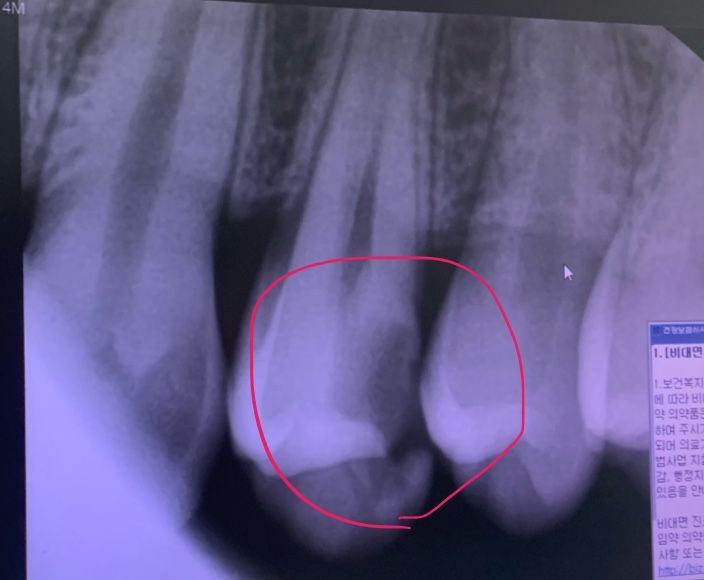

이가 썩어서 부서진 경우,,, 임플란트 해야하나요?

1월에 이에 구멍생겨서 치료받아야한다고 했는데 바빠서 못가고 있었고 치실로 관리만 최대한 하고있었는데

오늘 밥먹다가 먼가 허전해서 보니까 이가 깨졌어요;;;;

(1월때 사진)

1월에 신경치료 해야한다했었는데 임플란트 해야하나요??

지금은 임플란트 하기보다는 신경치료 및 크라운 치료를 통해서 치아를 살릴 수 있을 것으로 보입니다.

사진으로 봤을 경우에는 충치가 깊긴 하지만 발치를 할 정도는 아닌 것으로 보입니다. 충치를 제거하고 신경 치료를 한 뒤에 크라운 치료를 하면 될 것으로 생각됩니다. 자세한 확인을 위해서 치과에서 진료를 받아보는 것을 권해드립니다

저정도라면 일단 신경치료를 하고 크라운 치료를 해볼것같습니다. 발치하기에는 조금 치아가 아깝긴 하네요.

뿌리가 손상되지 않은 경우에는 크라운으로 씌우는 치료가 가능하나, 만약 뿌리가 손상이 된 경우에는 임플란트가 필요로 됩니다.

보다 정확한 상태 확인을 위해 치과 진료를 빠른시일내에 받길 권합니다.

깨져나간부위가 깊어 신경치료는 피할 수 없을 것 같습니다 그나마 다행인건 잇몸위쪽으로 깨져있어서 치아 예후가 그렇게 안 좋진 않습니다 아직 발치 단계는 아닙니다